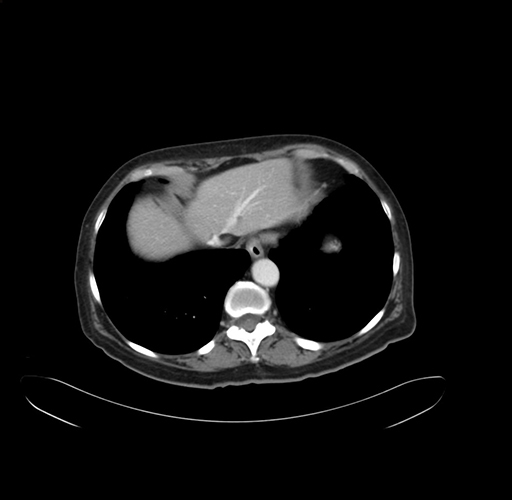

Pre-Chemo: Axial Venous